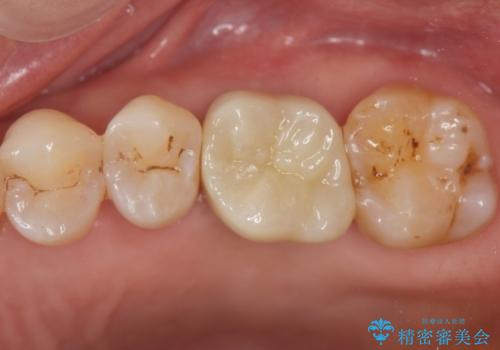

- 歯が割れてしまい、抜歯後のインプラント治療を希望され相談来院されました。

歯の喪失後に失われた咬合機能を回復するため、ブリッジ・入れ歯・インプラントの治療提案を行いました。

それぞれの長短所を検討し、隣接する歯を削らずにすみ、咬合機能をもっともしっかり回復できるインプラント治療を希望されました。